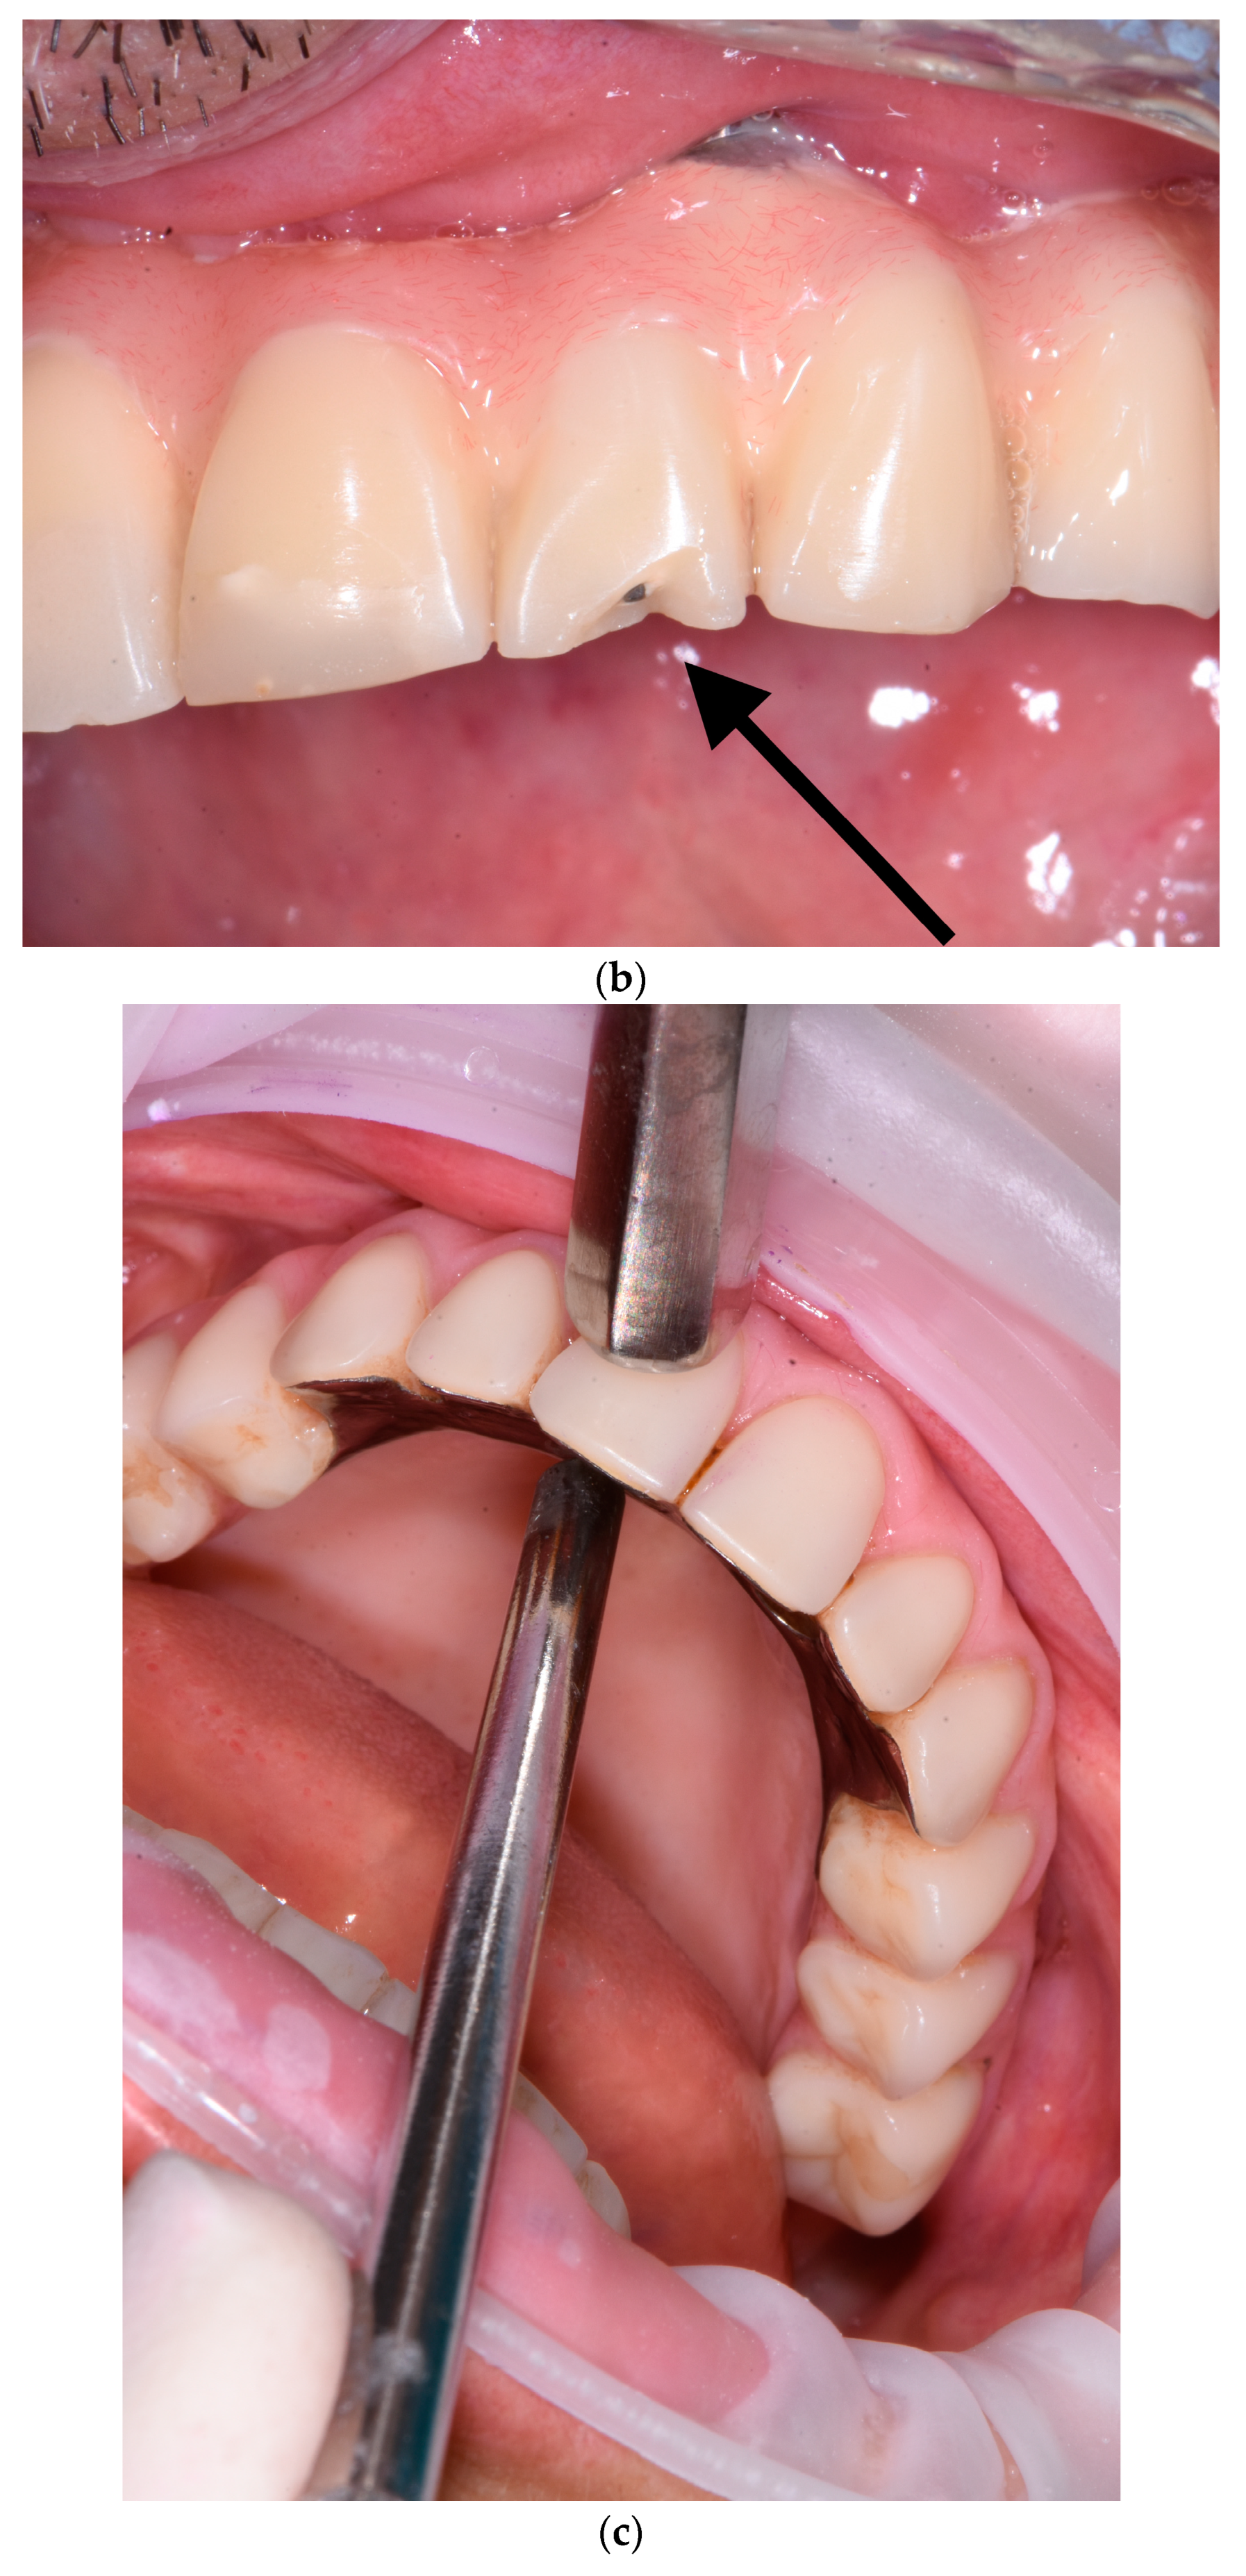

Detecting mechanical issues during the first year of function of the implant-supported prosthodontic device is of utmost importance to prevent biomechanical complications that may compromise osseointegration and lead to inflammation in the peri-implant mucosal tissue. The healthcare provider overseeing the patient’s progress during this phase should possess the expertise to identify prosthodontic abnormalities and promptly communicate them to the specialist. In this perspective, the fourth step consists of the examination of prosthodontic structures to identify occlusal wear (Figure 6a), chipping (Figure 6a), fracture lines (Figure 6b), horizontal and vertical mobility (Figure 6c), and hygienic access to the prosthesis (Figure 6d). If occlusal problems are identified, then initially the opposing arch is assessed, and then the implant prosthesis is removed, followed by reassembly in an articulator to reassess masticatory movements. Repairs are carried out in case of chipping and, if necessary, palatal metal protection is added.

Figure 6.

(a–d) Intraoral pictures of possible technical complications of zygomatic implants: chipping and occlusal wear (a), prosthesis fracture (b), vertical mobility (c), challenging access for hygienic devices (d).

The materials used in this phase are spongy dental floss and optical magnifiers.